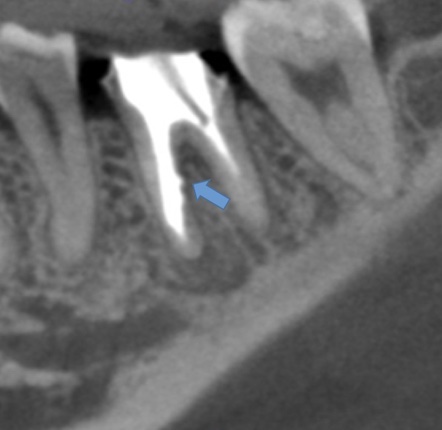

かぶせ物が不適であること(青矢印部)、近心根に根尖病巣があること(青枠部)、根充剤がかなり太いため(赤矢印部)歯質が薄くなっていることなど問題点がいくつかありましたが、他院で治療をしたばかりであり、また上記の条件から再治療には抜歯のリスクが非常に高いことから初診時は患者さんと相談し経過観察することになりました。